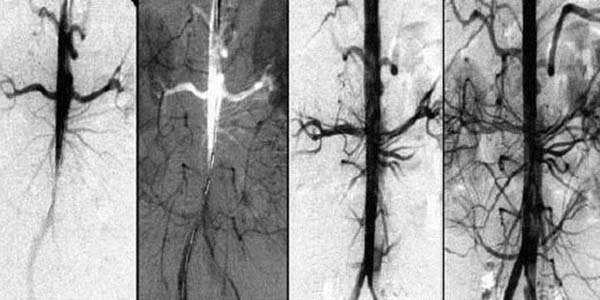

– Gibt es Möglichkeiten, die Blutgefäße zu reinigen und die Durchblutung selbst zu verbessern?

– Ja, aber sie erfordern in der Regel Geduld, Disziplin und eine gesunde Lebensweise. Viele

Aktivitäten wie regelmäßige körperliche Betätigung, eine gesunde Ernährung und der Verzicht

auf schlechte Gewohnheiten wie Rauchen oder übermäßigen Alkoholkonsum können dazu beitragen,

die Durchblutung zu verbessern und die Blutgefäße zu stärken.

Das Nationale Medizinische Zentrum für Gefäßchirurgie und Kardiologie hat ein einzigartiges

Mittel, namens Dr.Cardio, entwickelt. Es wurde von Experten des Instituts erstellt und kann